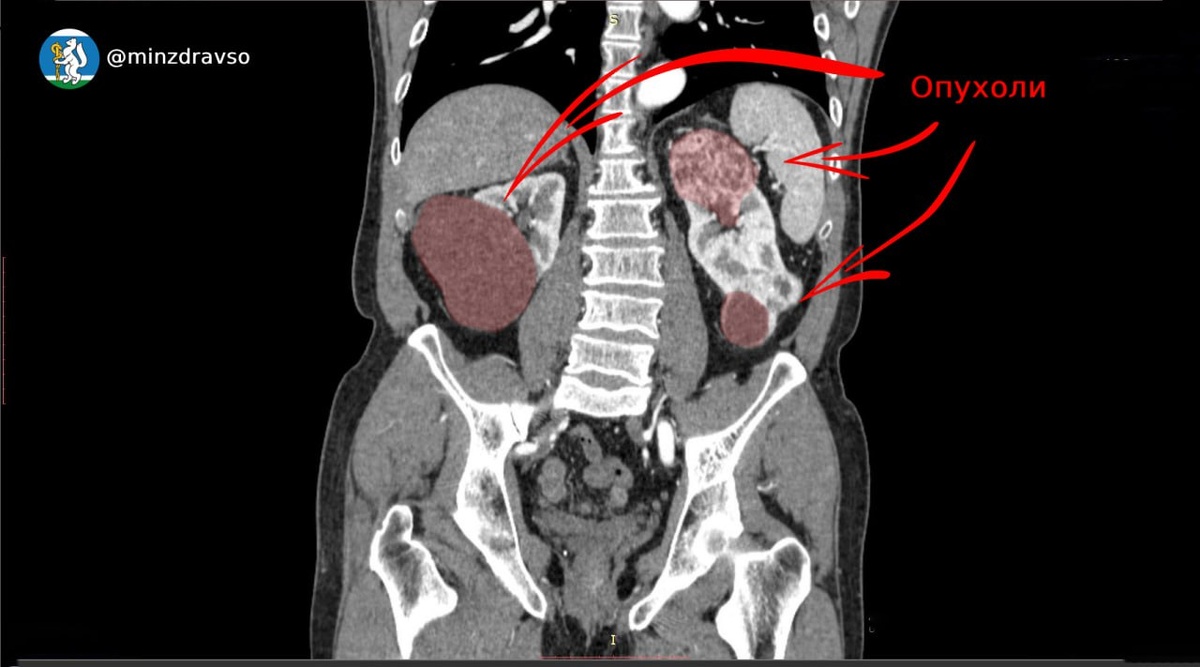

⚡️Свердловские онкоурологи спасли пациента с редким синхронным раком почек. Такой синхронный рак, когда обе почки были поражены объёмными злокачественными новообразованиями, встречается редко — лишь в 2-6% случаев.

Наличие новообразования у свердловчанина заподозрил врач первичного звена системы здравоохранения в ходе планового медосмотра. Мужчину направили для углублённого обследования в Свердловский областной онкодиспансер, где врачи установили, что опухоль в правой почке диаметром более шести сантиметров распространилась почти на 50% паренхимы — важнейшего элемента почечной ткани.

👨‍⚕️Орган удалили, его функции взяла на себя левая почка, но и она была поражена опухолью. Чтобы максимально радикально удалить рак, при этом сохранив жизненно важную функцию почки, онкологи выполнили ещё одну операцию.

Два новообразования в оставшейся левой почке располагались в верхнем и нижнем сегменте. Это давало возможность сохранить 70% почечной ткани. Удаление опухолей суммарным размером 12 сантиметров выполнили успешно, с минимально короткой ишемией (необходимым снижением притока крови к органу) в 12 минут.